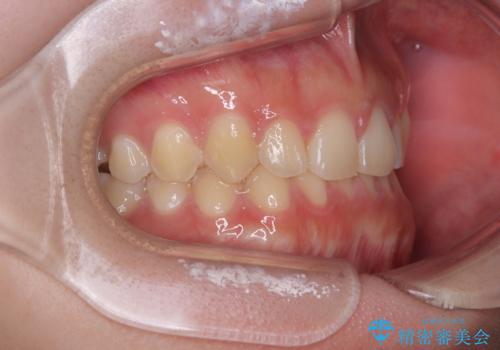

前歯のすきっ歯を治したい インビザラインによる矯正治療

- 上顎前歯の隙間を気にして来院された患者様です。

目立たない装置を希望とのことで、インビザラインを用いて矯正治療を行うこととしました。

最終的には隙間は全て閉じ、綺麗な仕上がりとなりました。